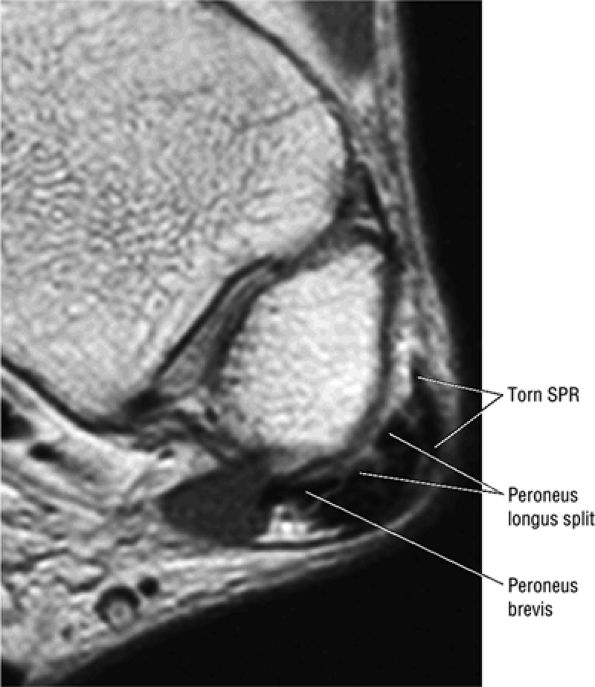

The peroneal retinaculum prevents the peroneal tendons from subluxing laterally over the lateral malleolus. Tears or stripping of the peroneal retinaculum from the lateral malleolus is inferred when subluxation or dislocation of the peroneal tendons is seen lateral to the lateral malleolus.